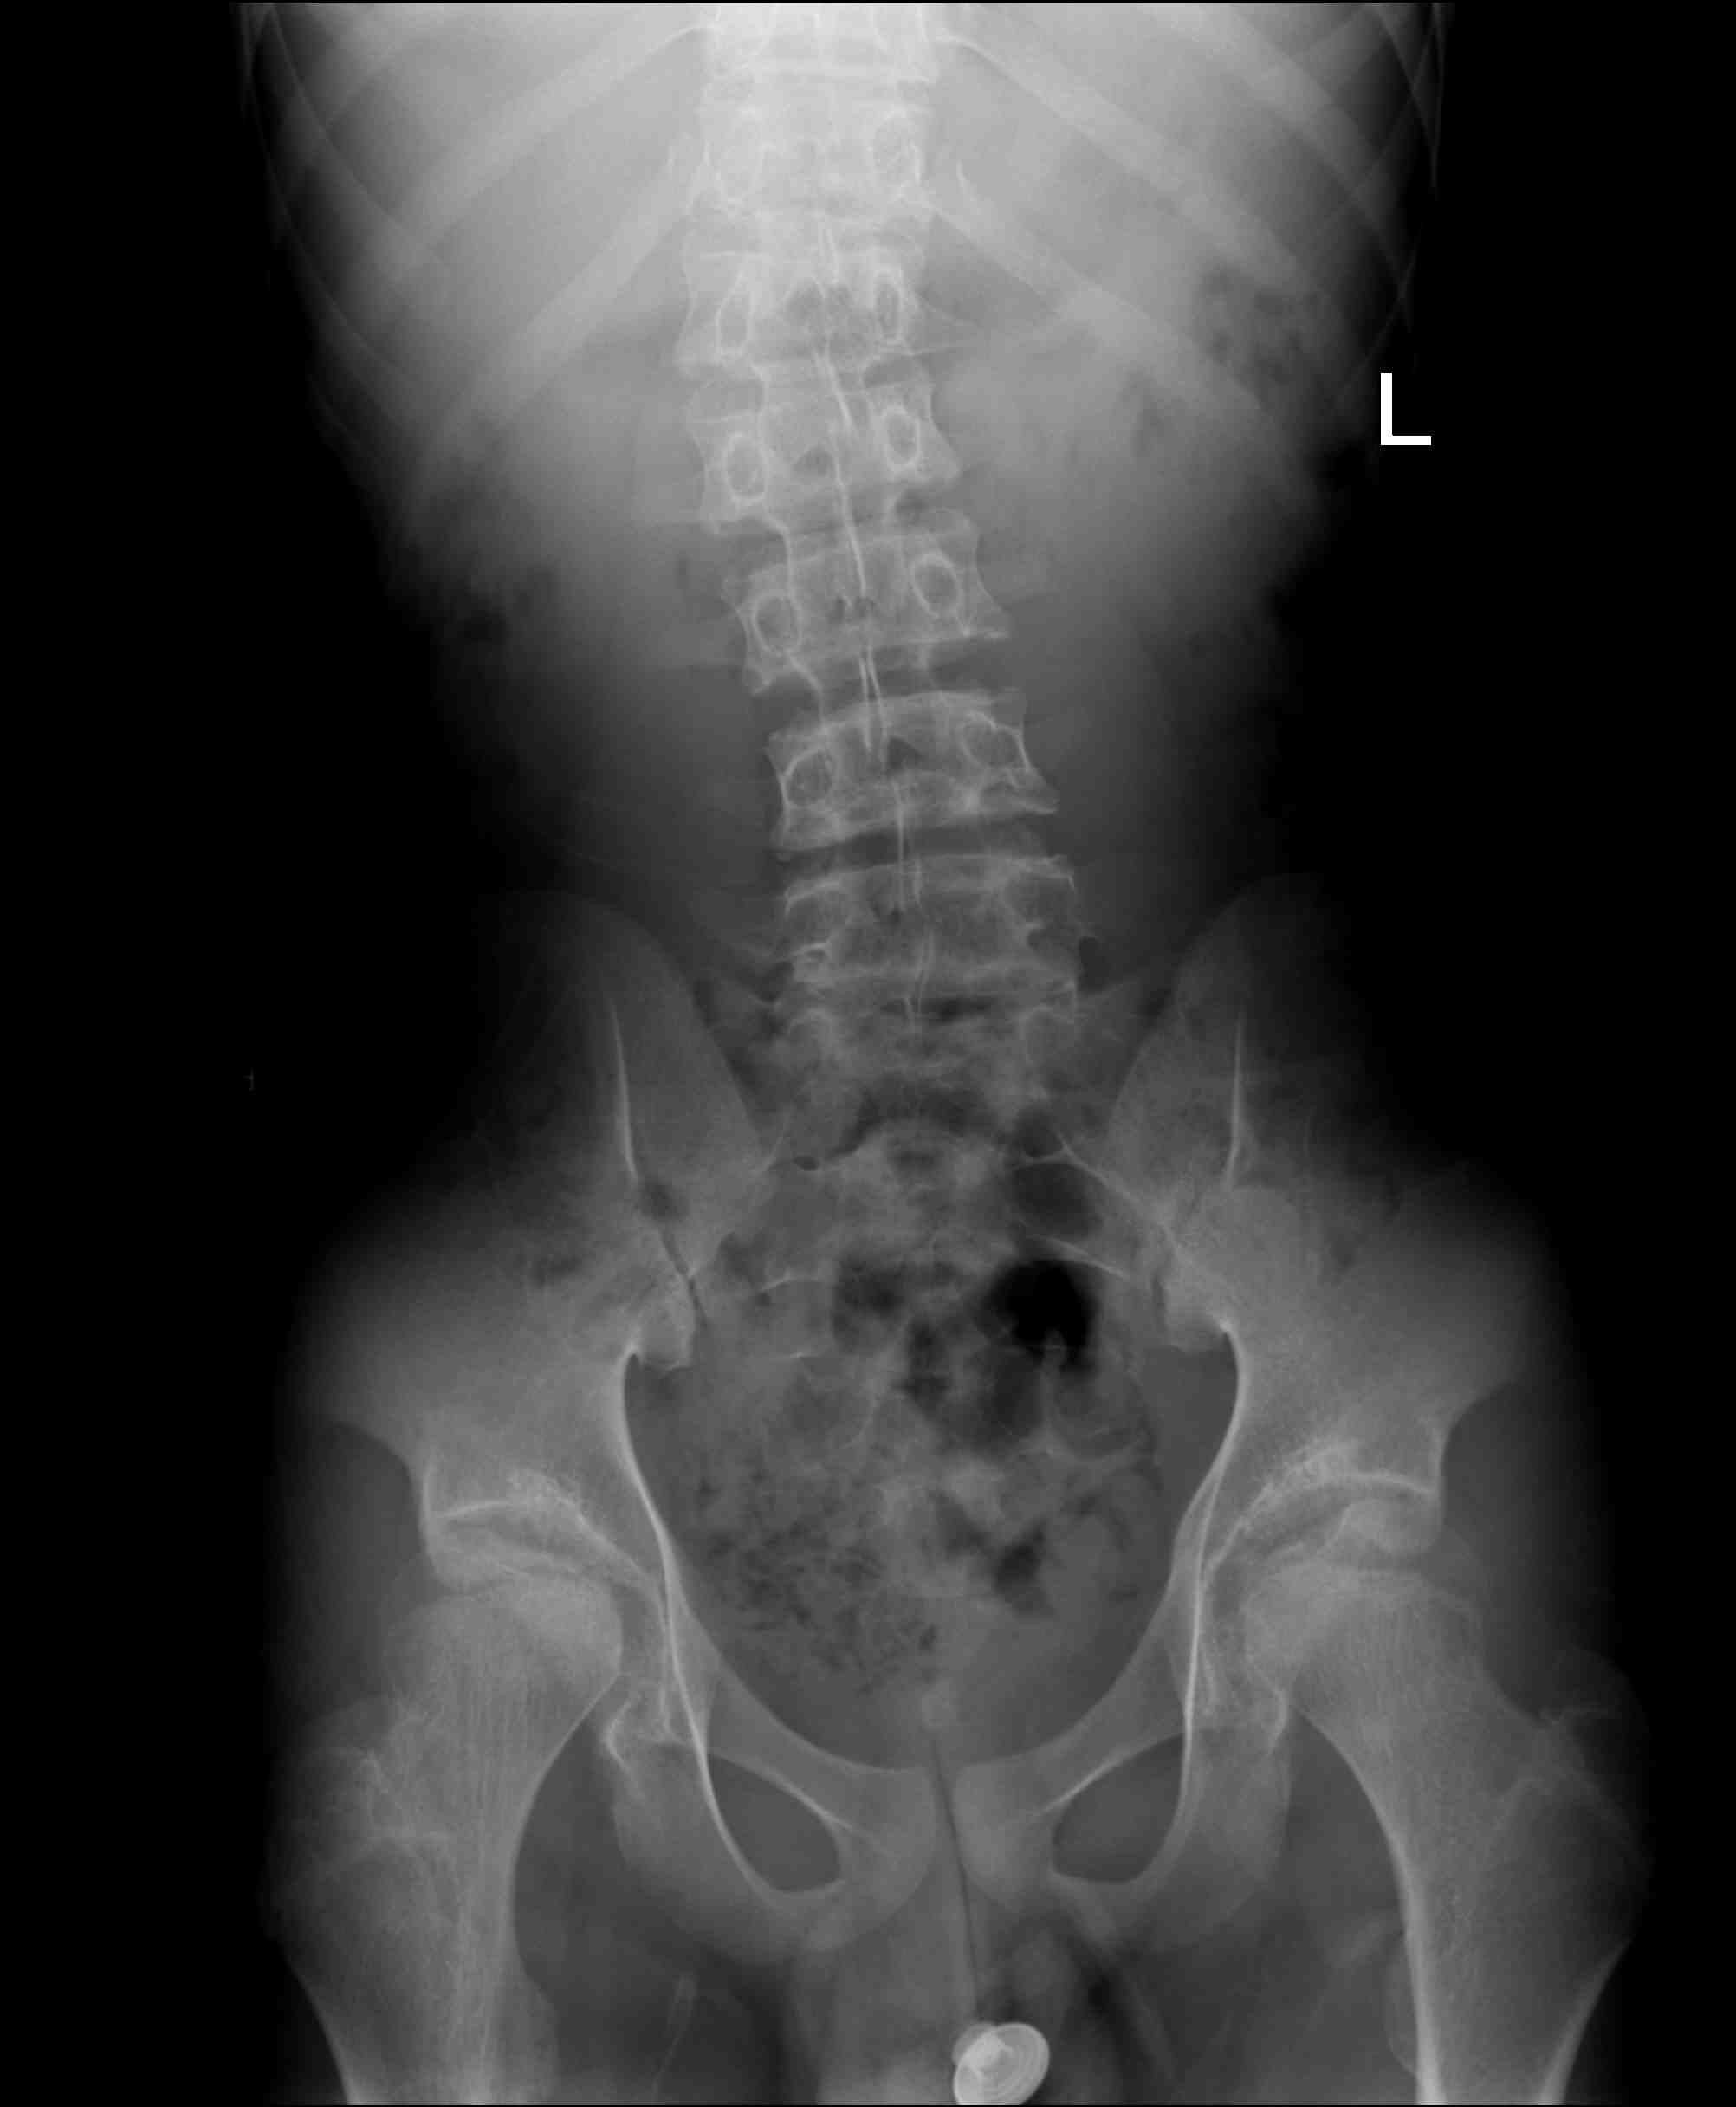

男 20岁 精神异常数年,摔倒后,腰背部疼痛,拍腰椎片。

scheuermann\"s病(休门氏病)即青少年脊柱圆背畸形。其发病原因尚不确定,男性多见,有家族性发病倾向。一 般认为与椎体的环行骨骺坏死有关。但有研究发现此骨骺与脊柱生长无关,不影响椎体的垂直生长,而且有患者在骨骺未出现前发病( 10 岁内)。本病的主要诊断依据为:青少年在胸椎中至少有 3 个相邻椎体有楔形变。x线显示胸椎中至少有3个相邻椎体有5 °或5 °以上的楔型改变,常伴有椎间隙变窄和schmorl 结节(许莫氏结节)。90% 的患者有椎体前后径增大。此病最常见的后凸位于胸椎,后凸顶点在中胸段。部分表现为胸、腰椎后凸,顶点位于胸腰段。患者出现后凸畸形的同时,可出现背痛,一般在停止生长后疼痛消失。若后凸加重并继发腰椎前凸加大,亦可出现下腰痛。